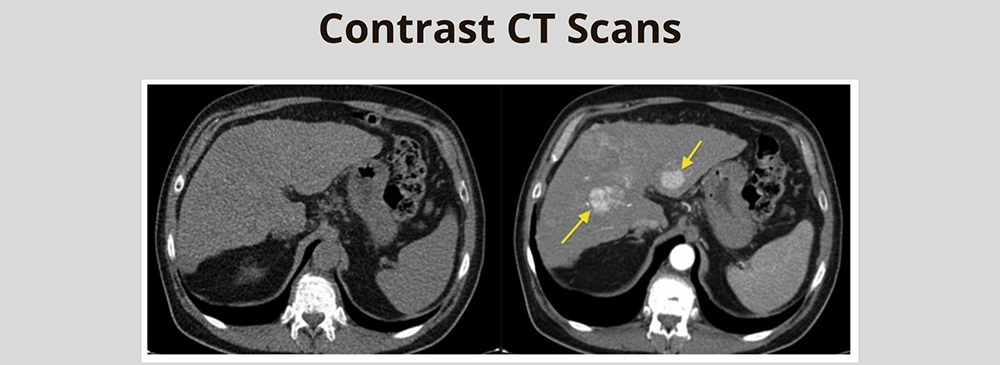

A Contrast CT Study is a specialized type of CT scan where a contrast dye is introduced into the body, usually by injection or oral intake, to make certain organs and blood vessels more visible. This helps doctors detect issues that might not appear on a regular scan.

There are times when a standard CT scan may not give the full picture your doctor needs. That’s when a Contrast CT Study in Pallavaram becomes essential. This advanced diagnostic tool is often recommended to examine blood flow, detect growths or abnormalities, monitor infections, or assess organ health. It’s also crucial in surgical planning, where precise imaging helps surgeons prepare with greater accuracy.

The value of a contrast CT lies in its ability to provide sharper and more detailed images than a standard CT scan. For many conditions, having this level of detail can be the difference between an early diagnosis and a missed opportunity for timely treatment. By showing precise outlines of organs, tissues, and blood vessels, contrast CT helps doctors pinpoint the exact size, location, and nature of a problem.